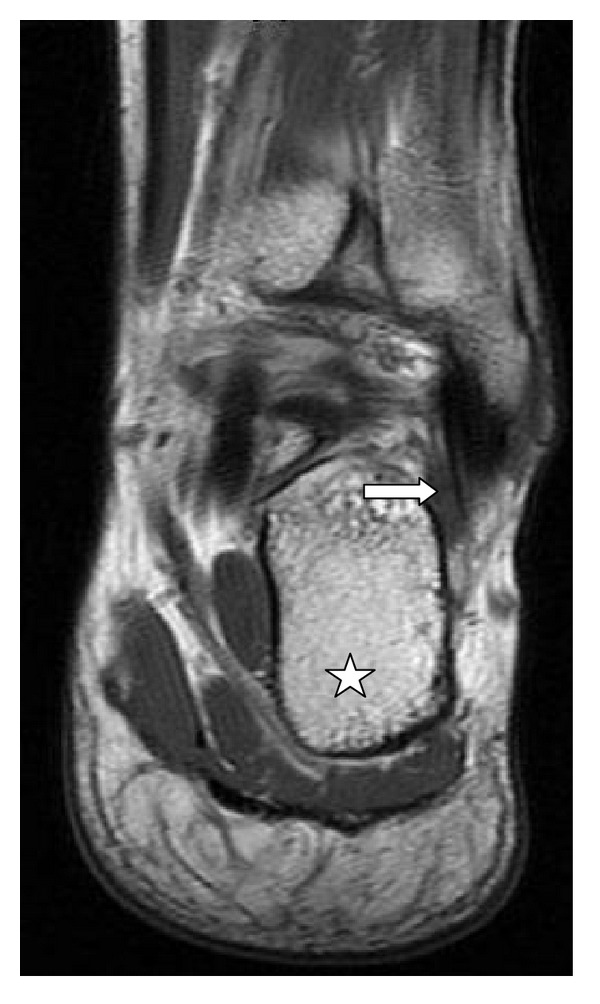

Objective. Quantify the presence of the fibularis quartus muscle and correlate it with the individual's sex and concomitant presence of the fibularis tertius muscle. Materials and Methods. We evaluated 211 magnetic resonance examinations (43.13% men and 56.87% women) on the ankle and hindfoot, produced between 2009 and 2011. Results. The fourth fibularis muscle was found to be present in 7.62% of the examinations and 75% of these also contained the fibularis tertius muscle. Conclusion. The incidence of the fourth fibularis muscle is variable; moreover, its incidence does not depend on the individual's gender or the presence of the fibularis tertius muscle.